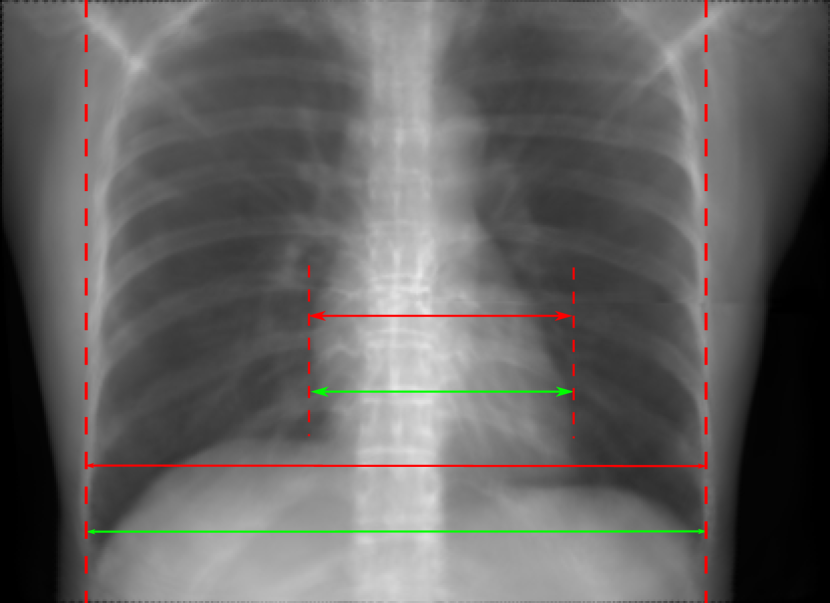

Figure 11: Perspective deformation learning in one exemplary patient case for cephalometric imaging. In (b), the left and right sides of the mandible do not overlap well, as indicated by the arrow. In (c), a scale bar of 2 mm is displayed (zoom in for better visualization), as 2 mm is the clinically acceptable precision for cephalometric landmark detection. In (e), (h) and (j), incorrect areas are marked by the red arrows.

TABLE III: Quantitative evaluation of different methods on head data.

Method Metric 0superscript00^{\circ} input 0superscript00^{\circ} 0&180superscript0superscript1800^{\circ}\&180^{\circ} 0&180superscript0superscript1800^{\circ}\&180^{\circ}

perspective Cart. Cart. polar

Pix2pix RMSE 10.69 7.33 4.58 3.87

GAN SSIM 0.8680 0.9053 0.9476 0.9625

Trans RMSE 10.69 8.13 3.36 3.22

U-Net SSIM 0.8680 0.9257 0.9682 0.9719

The results of one exemplary patient for cephalometric imaging are displayed in Fig. 11. In the 0superscript00^{\circ} perspective projection image (Fig. 11(b)), because of perspective deformation, anatomical structures from the left and right sides do not overlap well, especially for the mandible as indicated by the red arrow in Fig. 11(b). It causes inaccuracy in determining the cephalometric landmark of the gonion. The difference of Fig. 11(b) to the reference Fig. 11(a) is displayed in Fig. 11(c). A scale bar of 2 mm is displayed in Fig. 11(c), as 2 mm is the clinically acceptable precision for cephalometric landmark detection. It is obvious that many anatomical structures in the 0superscript00^{\circ} perspective projection images have position shifts larger than 2 mm. In the prediction image (Fig. 11(d)) using a single 0superscript00^{\circ} view in Cartesian coordinates, perspective deformation is reduced to some degree, as displayed in the difference image Fig. 11(g). For example, the mandible region has less error. However, Fig. 11(g) also indicates that many bony structures still have deviations larger than 2 mm. The results of learning from dual complementary views in Cartesian and polar coordinates are displayed in Fig. 11(e) and Fig. 11(f), respectively. Both images have little perspective deformation, as revealed by their difference images in Fig. 11(h) and Fig. 11(i). Nevertheless, in Fig. 11(e), two dark regions are indicated by the two arrows, which are better visualized in the difference image Fig. 11(h). The results of TransU-Net are displayed in Figs. 11(j)-(o). In Fig. 11(m), the structures near the porion landmark are distorted, for example, the ear canal indicated by the arrow. Consistent with Pix2pixGAN, perspective deformation is largely reduced in the both TransU-Net prediction images using dual complementary views in Cartesian and polar coordinates.